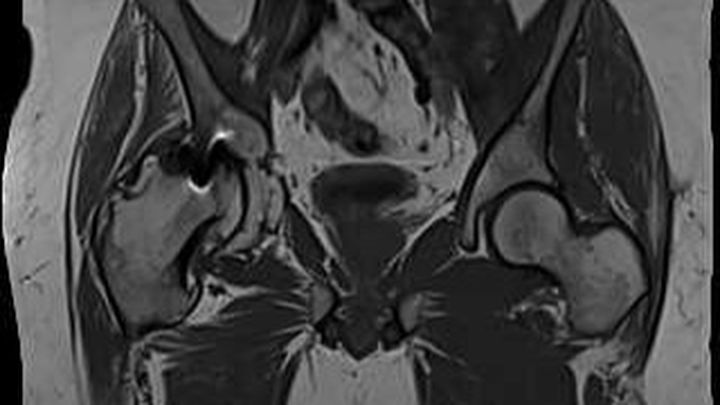

Yesterday, we finally saw why. The MRI revealed something devastating: there is absolutely no cartilage left in Zach’s hip. None. The hip ball is severely damaged and deteriorated. It is completely bone on bone. Severe arthritis has eaten away much of the joint. Fragments of bone are floating around in his body. The image is honestly hard to look at. The hip on the right side of the photo is his normal hip. Now look at the deterioration and malformation and disfigurement of the hip on the left side of the photo. There is virtually no "ball" socket left and the entire hip is severely deformed.